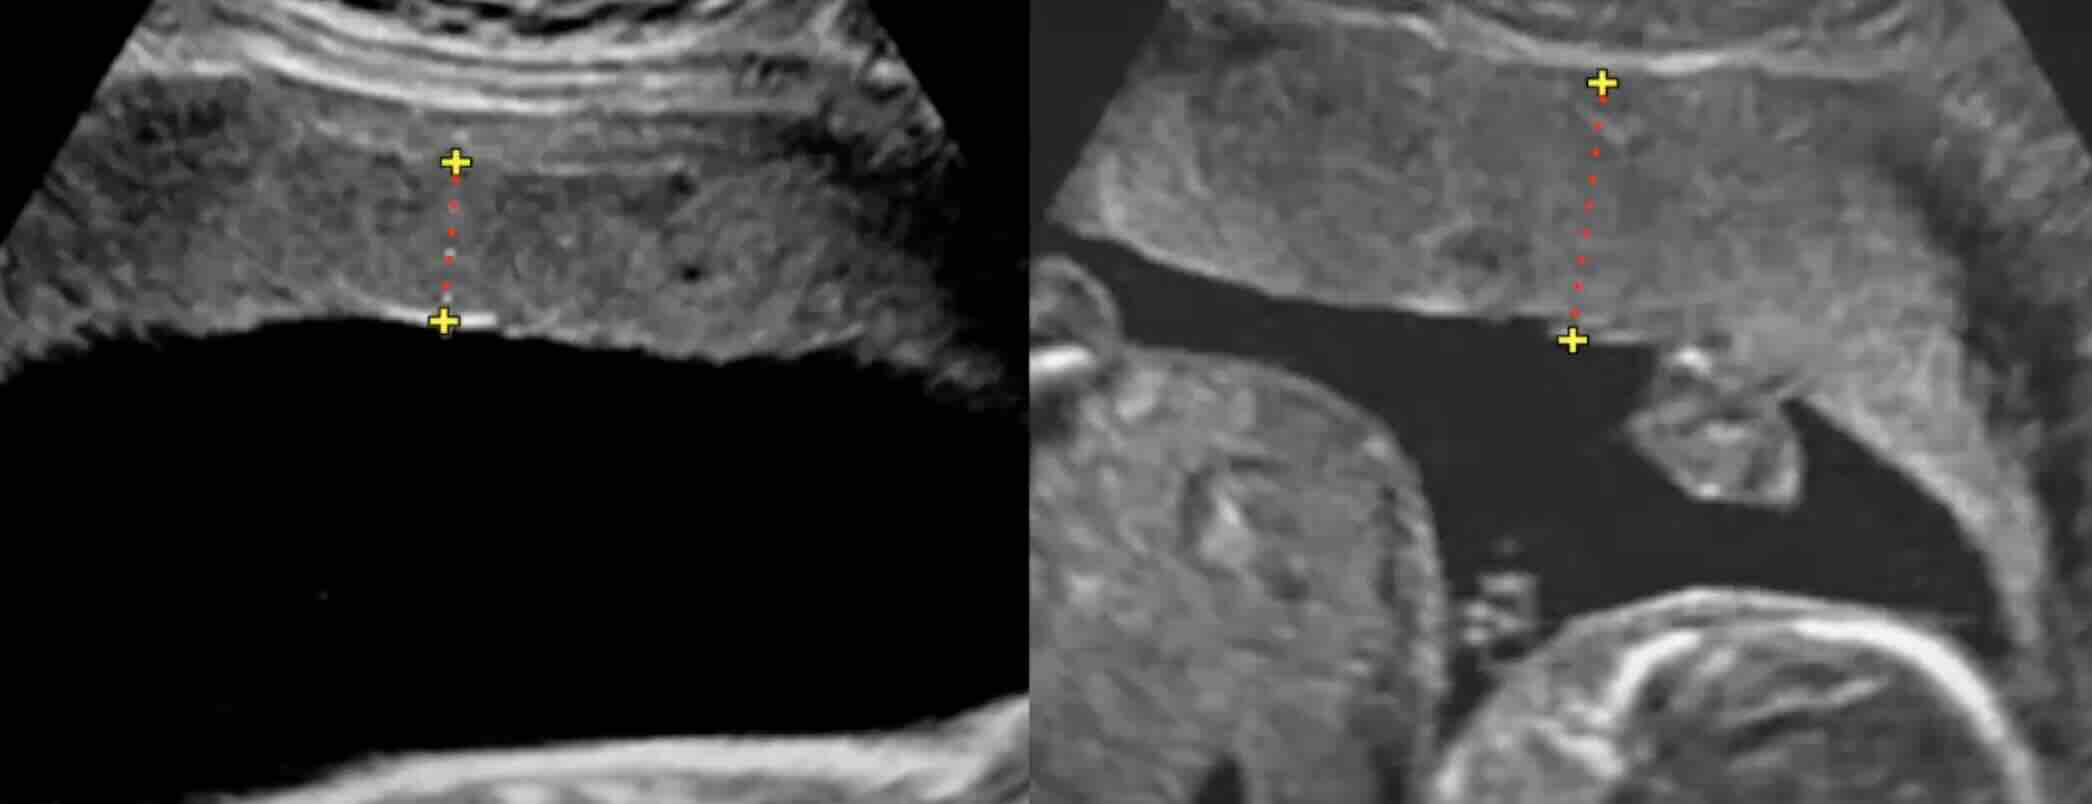

- Daha önce LEEP veya konizasyon gibi bir CIN tedavisi görmüş olmak, nadiren de olsa erken doğum veya servikal yetmezlik riskini bir miktar artırabilir. Bu nedenle, böyle bir geçmişiniz varsa gebelik takibinizi yapan doktorunuzu mutlaka bilgilendirmelisiniz. Doktorunuz gebelik sırasında rahim ağzı uzunluğunuzu ultrason ile takip edebilir.